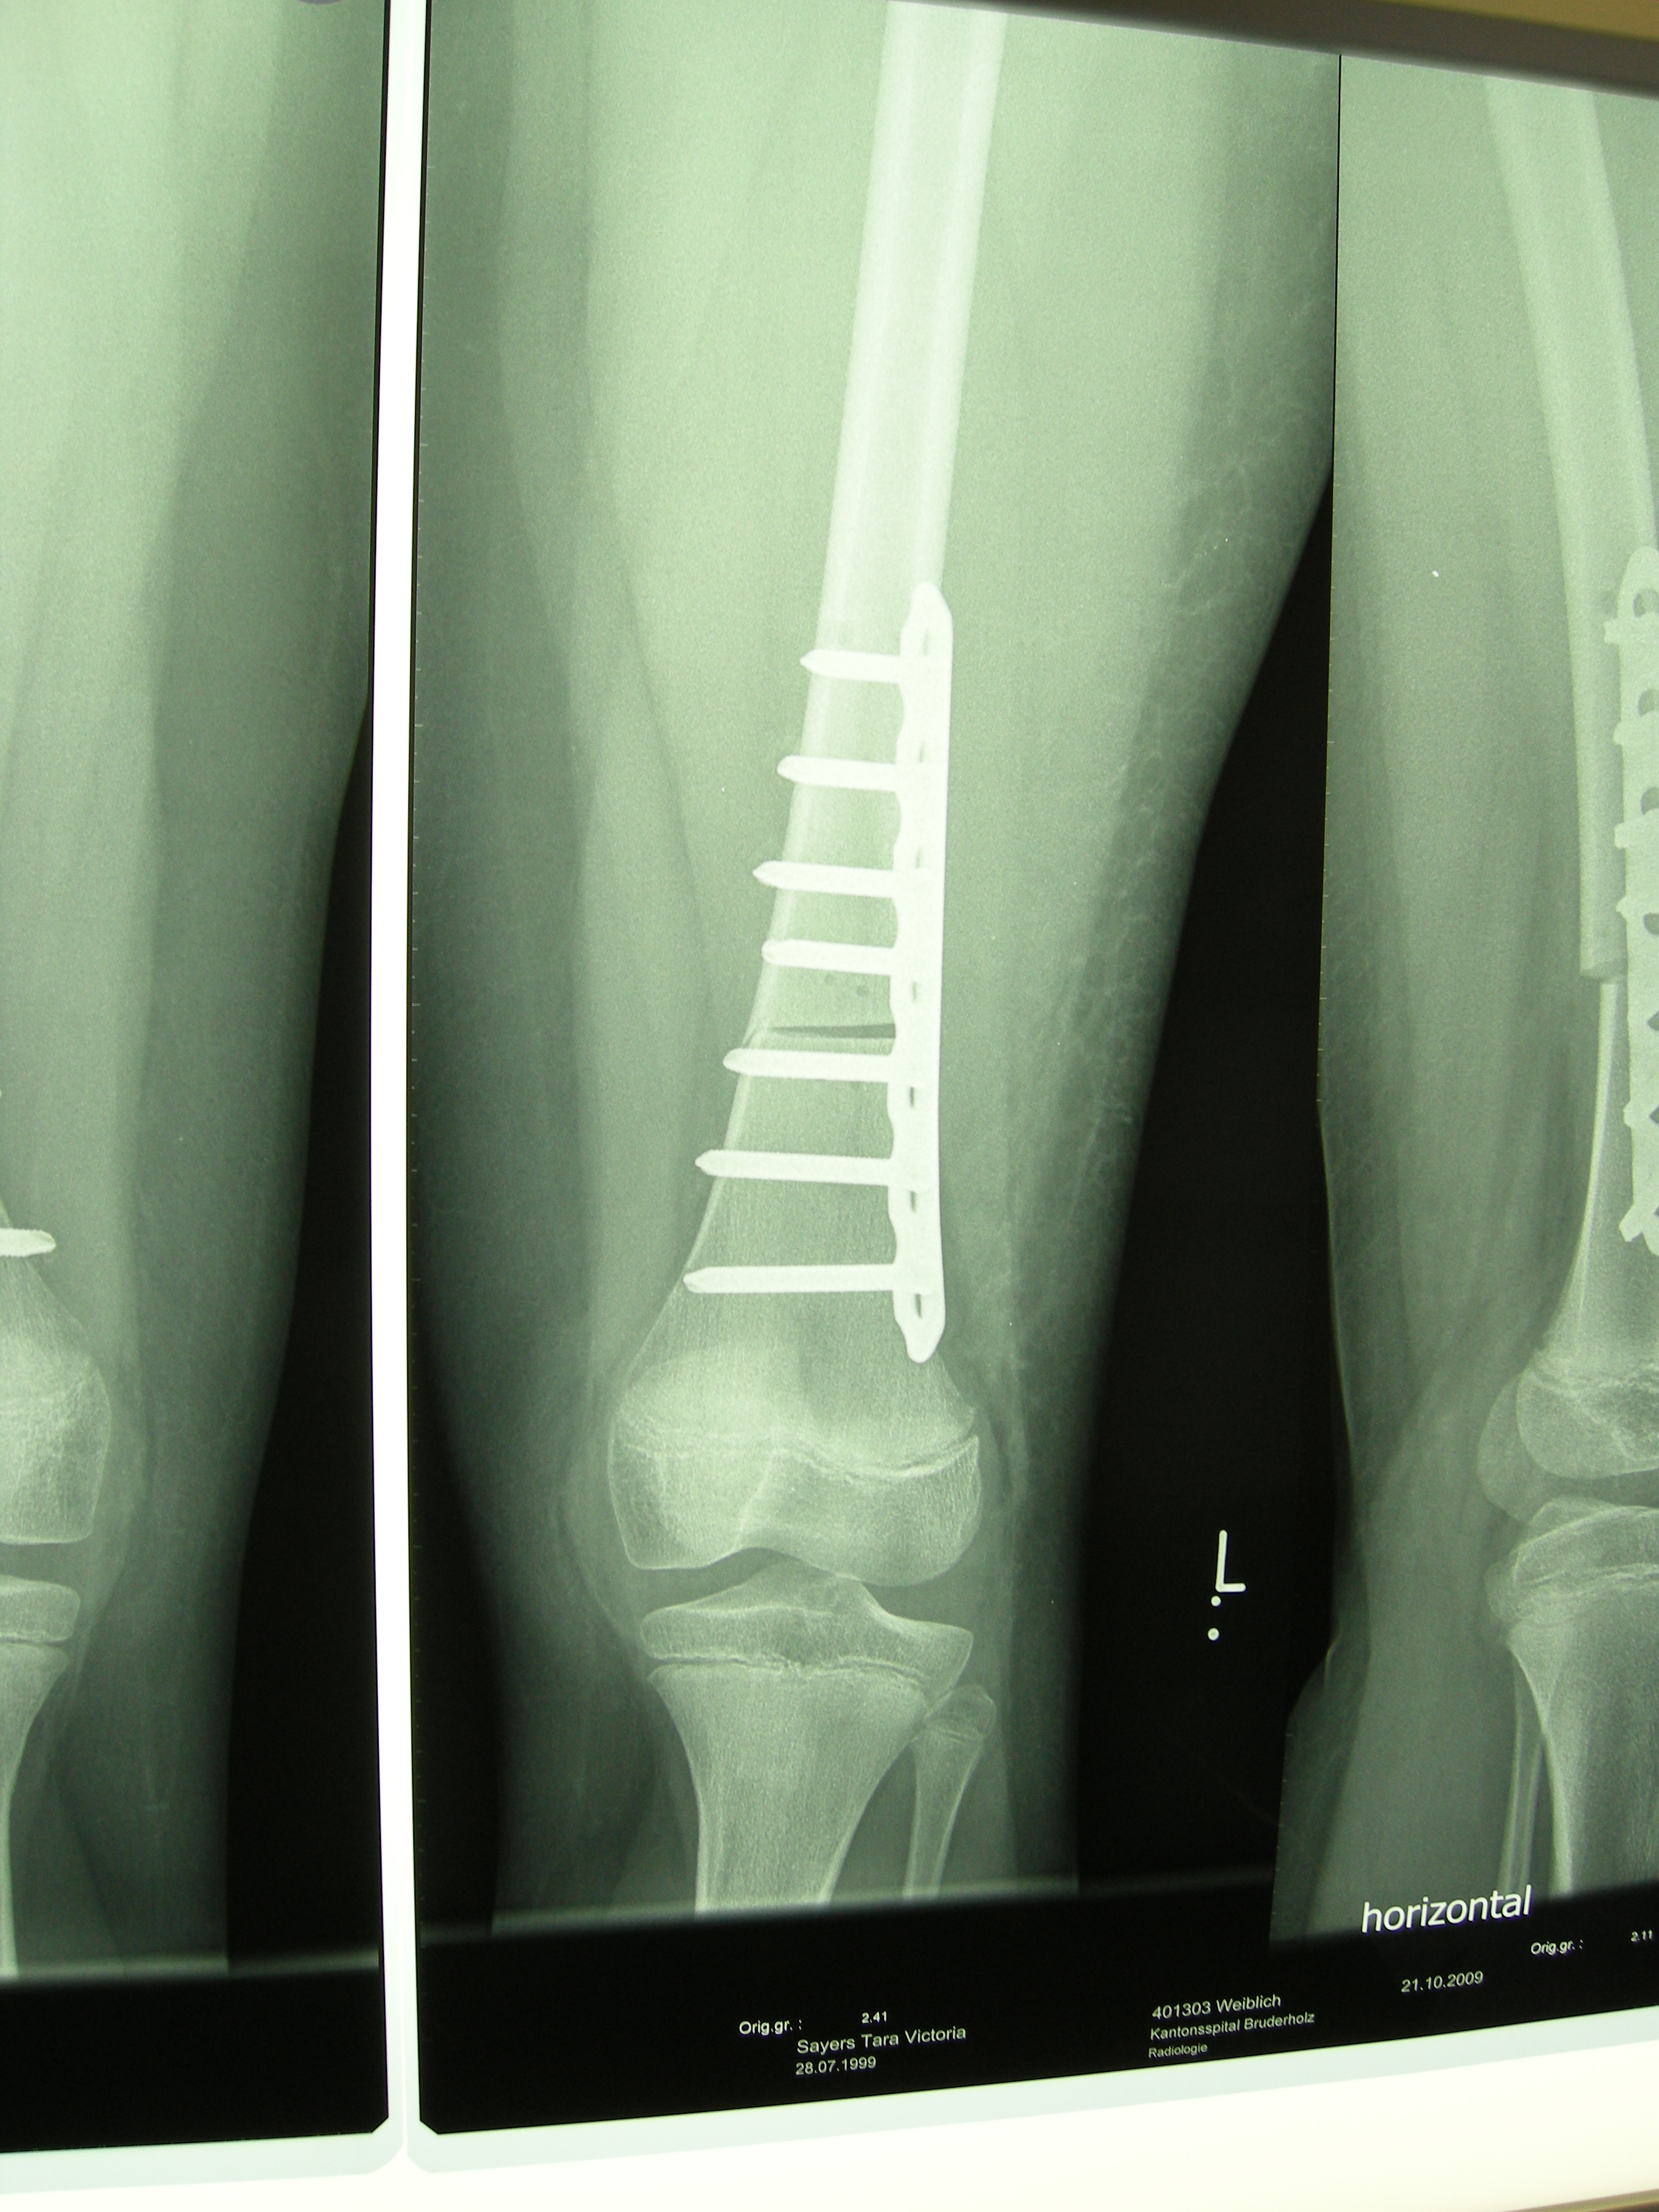

XRays